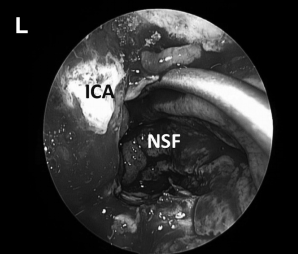

▼(L)使用鼻中隔瓣 (NSF)完成封闭。CC,囊包膜;PFD,后颅窝硬脑膜;S,蝶鞍;T,肿瘤。